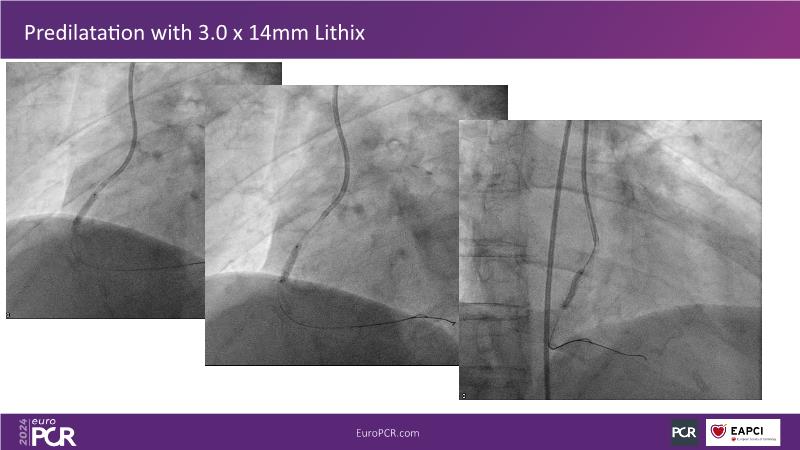

Follow this session to learn about the novel HC-IVL system, its application for moderate to severe calcified lesions, and procedural tips. The LithiX Hertz Contact IVL addresses unmet needs in coronary artery calcification by offering a simplified workflow with fewer devices and effective treatment for difficult lesions. Its novel design ensures safety and efficacy, with the PINNACLE I study's primary outcomes expected to confirm its effectiveness.